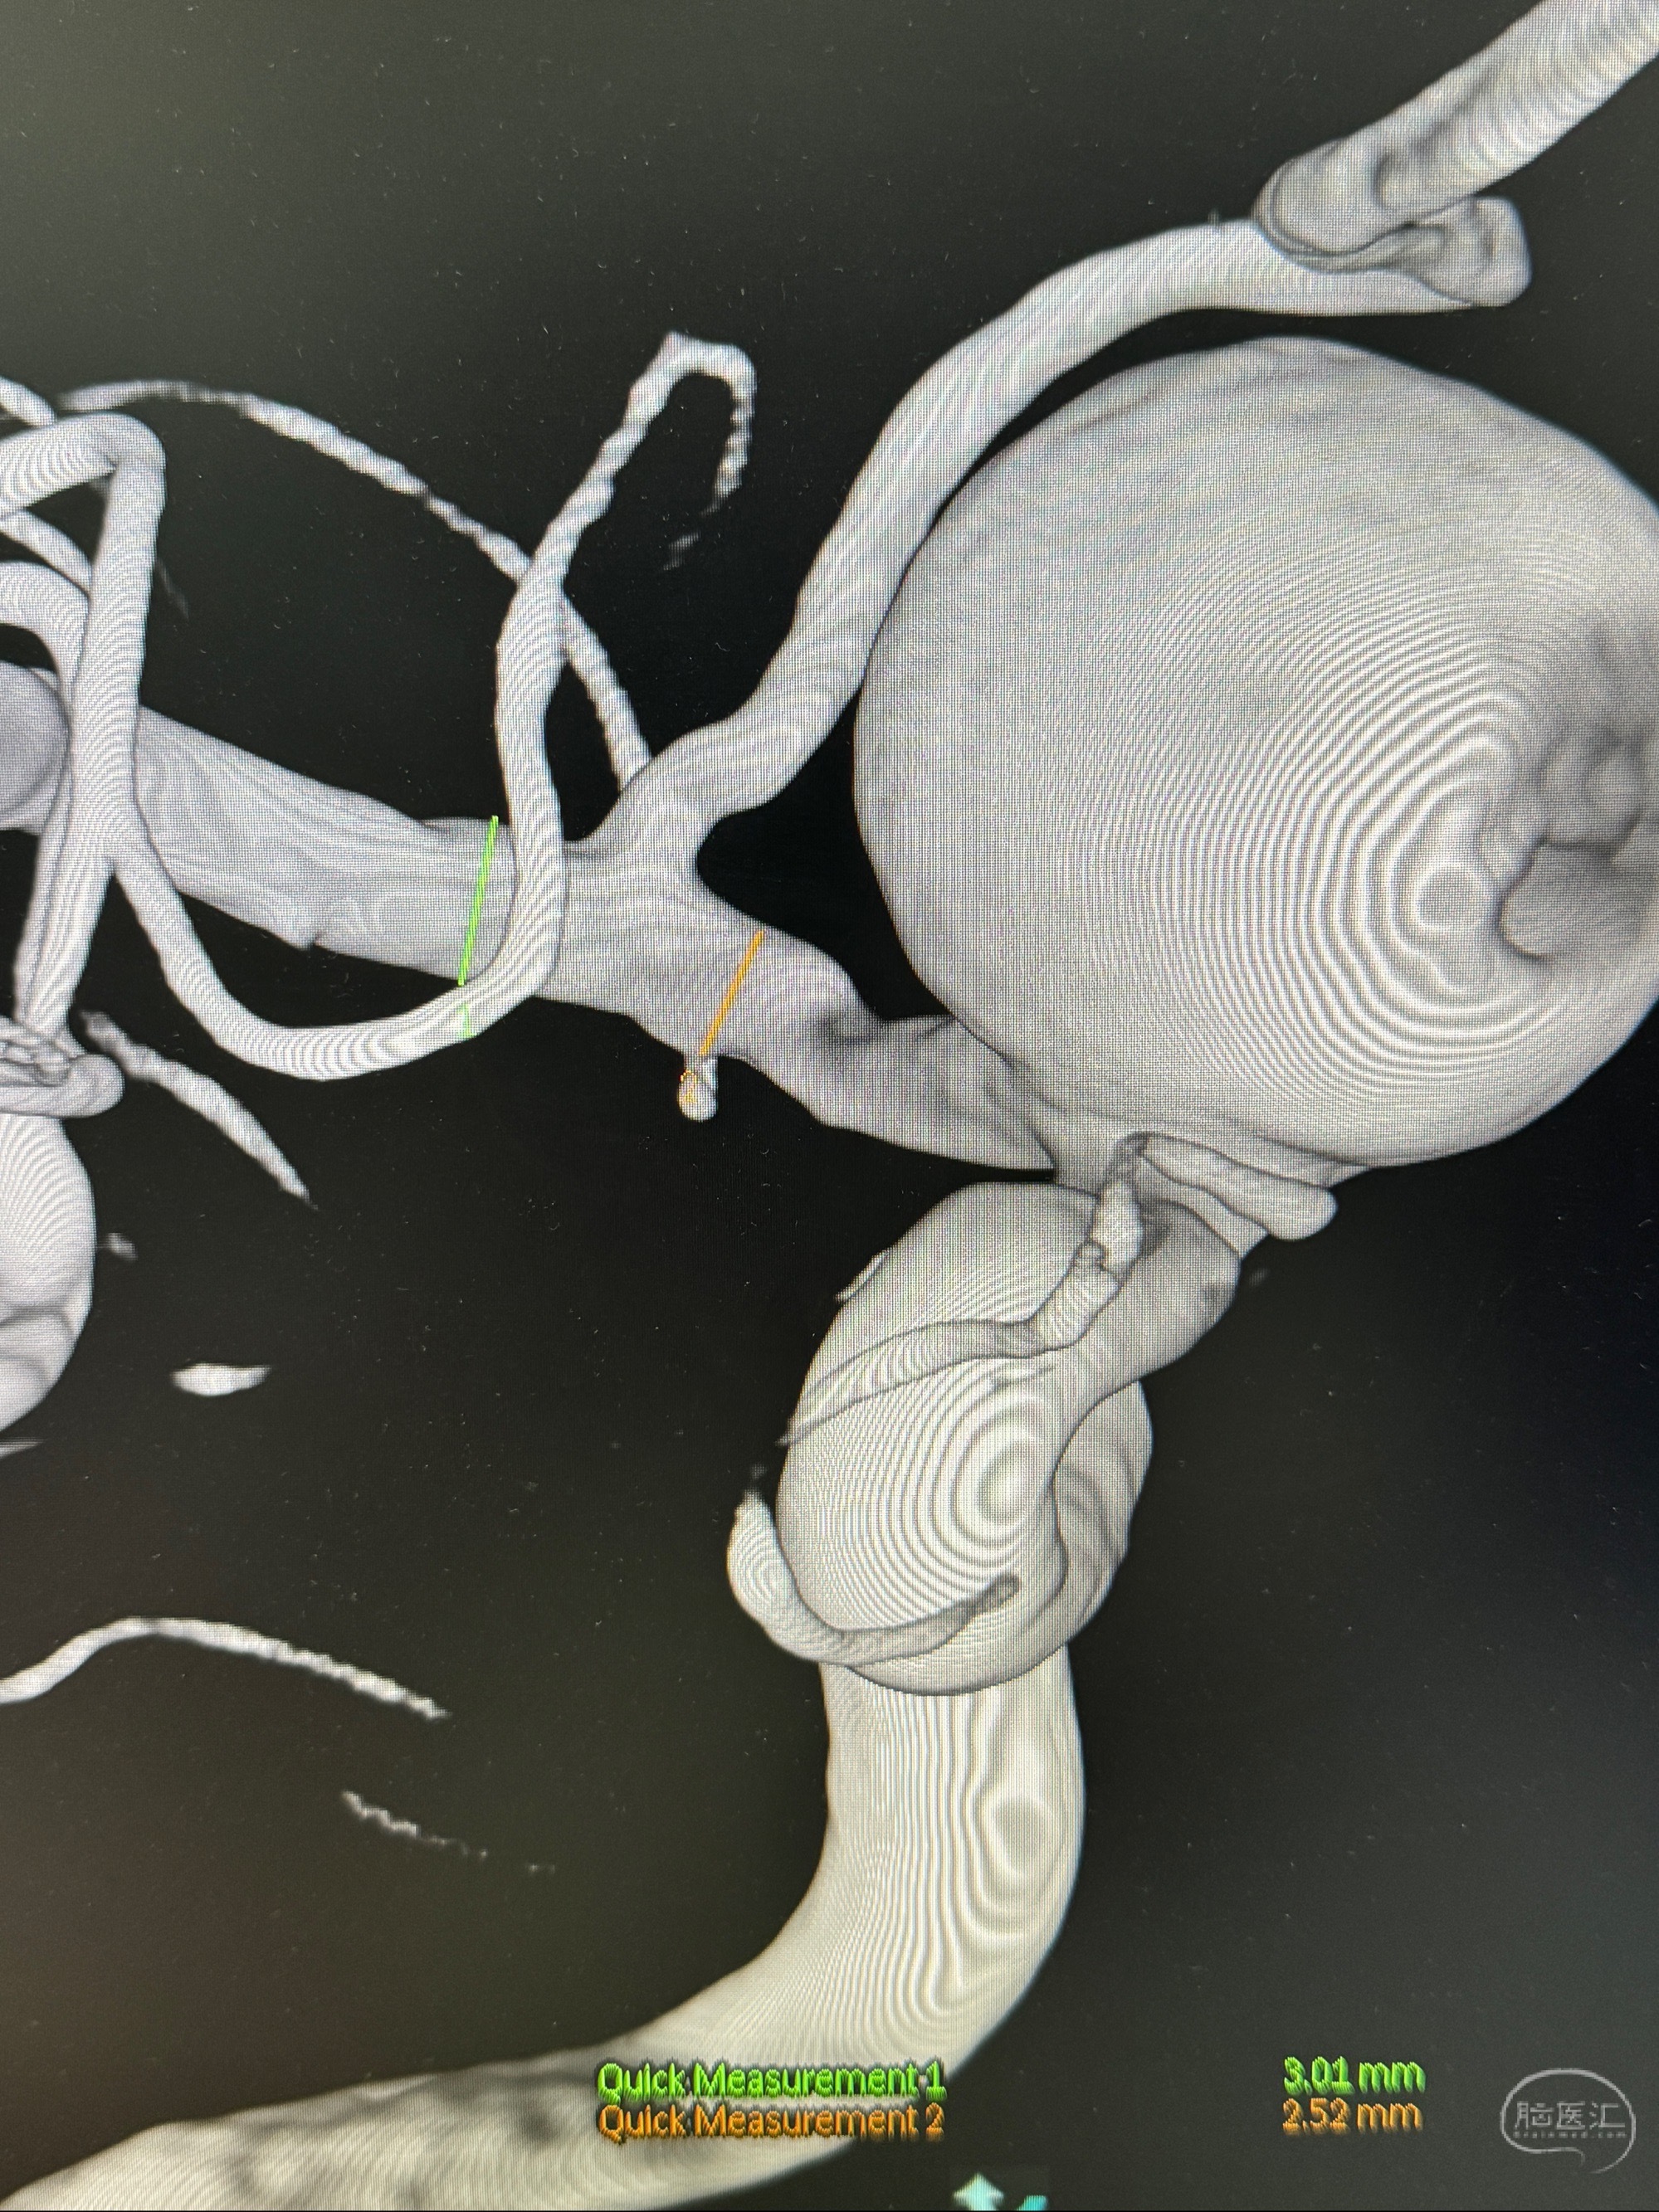

旋转3D展示动脉瘤局部的血管构筑

测量动脉瘤的大小:16*13.8*7.6mm大小,较原先变大,考虑双抗后瘤内血栓溶解可能

4.5-30mmTurbridge密网支架,于M1近心端打开

Tubridge 4.5-35mm